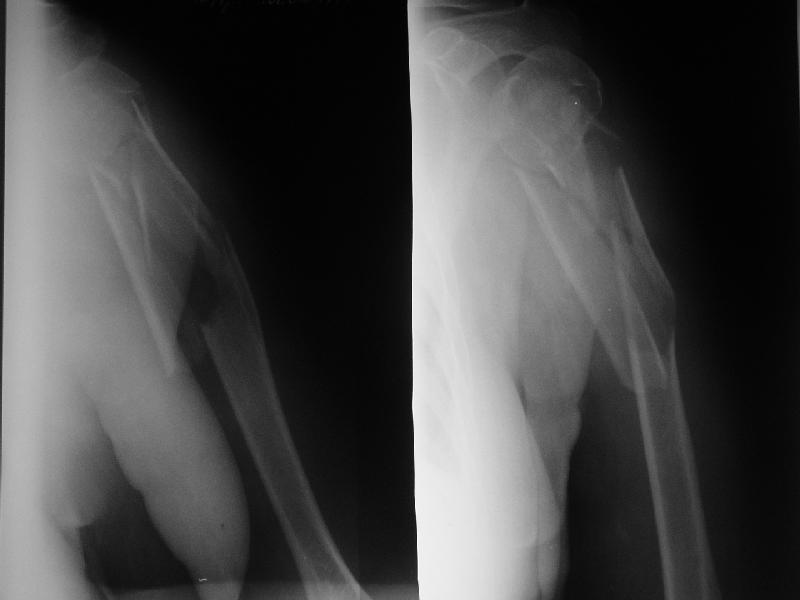

Re: Оскольчатый перелом плеча

Djoldas Kuldjanov 17 Август 2006, 14:00

Доминирующая ли рука и какая профессия?

Если выбор на интрамедулярный штифт, я бы сделал КТ головки, информация необходима для определения вовлечения головки в перелом, имеется опасность

расколочения и для ориентира расположения блокирующих шурупов.

"Рука не доминирующая, но тоже нужна" - А.Н. Челноков. Больная уже лечилась консервативно в гипсовой повязке и на вытяжении, в настоящее время настаивает на оперативном лечении.

Есть и другие косые снимки, на которых не определяется вовлечение головки, если успеем - сделаем КТ. Спасибо за интерес к нашему случаю.

Ув. коллеги. Интересно, насколько разрушена головка, особенно ее артикулирующая поверхность, может для начала сделать КТ головки.

На счет операции - стоит ли ее вообще делать, куда Вы собираетесь забить стержень, на расколете ли головку, если она еще целая. В любом случае Вы

не добъетесь стабильной фиксации, прийдеться иммобилизировать где-то на месяц. Вопрос: какова будет функция после травматичной операции, а она

имеенно таковой будет и последующей иммобилизации. ВЧКДО сделать не получиться - не за что зацепиться.

> Ув. коллеги. Интересно, насколько разрушена головка, особенно ее

> артикулирующая поверхность, может для начала сделать КТ головки.

По нескольким снимкам в чуть разых проекциях она не фрагментирована. А если и были трещины, за прошедшие 3 недели они "слиплись", очевидно. А КТ если сделаем - еще можем испугаться увиденного :-)